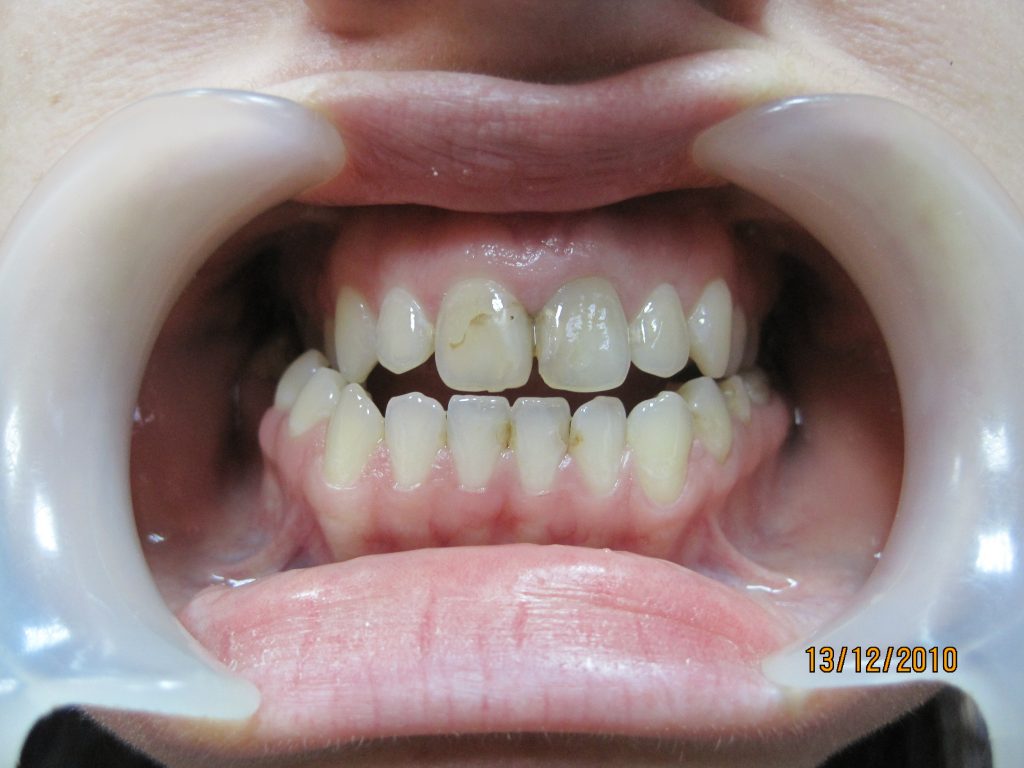

Progenia (przodożuchwie morfologiczne, prognatyzm żuchwy) jest wadą czaszkowo-szczękowo-zgryzową polegającą na nadmiernym wzroście doprzednim żuchwy w stosunku do szczęki (5, 7).

Wada ta wpływa negatywnie nie tylko na wygląd twarzy – wysunięcie bródki oraz dolnej wargi, lecz również może prowadzić do wystąpienia różnego rodzaju zaburzeń czynnościowych, w tym dysfunkcji stawów skroniowo-żuchwowych (1-3).